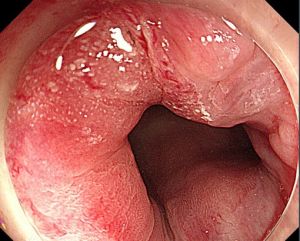

3.腸鏡或肛門鏡觀察到典型鏡下表現

1.內痔好發部位為截石位3、7、11點。主要表現為出血和脫出。內痔的常見臨床症狀是間歇性便後出鮮血。部分患者可伴發排便困難。當內痔合併發生血栓、嵌頓、感染時則出現疼痛。

Ⅳ度,偶有便血,痔脫出後不能還納或還納後再次脫出。均可伴有齒狀線區黏膜糜爛,小血管裸露,肛裂等。

3.混合痔是臨床上最主要的發病形式,內痔和外痔的症狀可同時存在,主要表現為便血、肛門疼痛及墜脹、肛門瘙癢等。